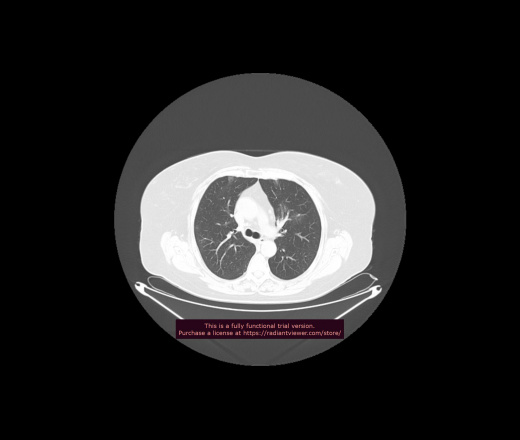

Уважаемые коллеги, если имеется интерес, сможете ли Вы спрогнозировать дальнейшее +-одинаковое течение процесса у 4 данных разных пациентов? Зацепиться где-то можно очень просто, где-то нельзя.